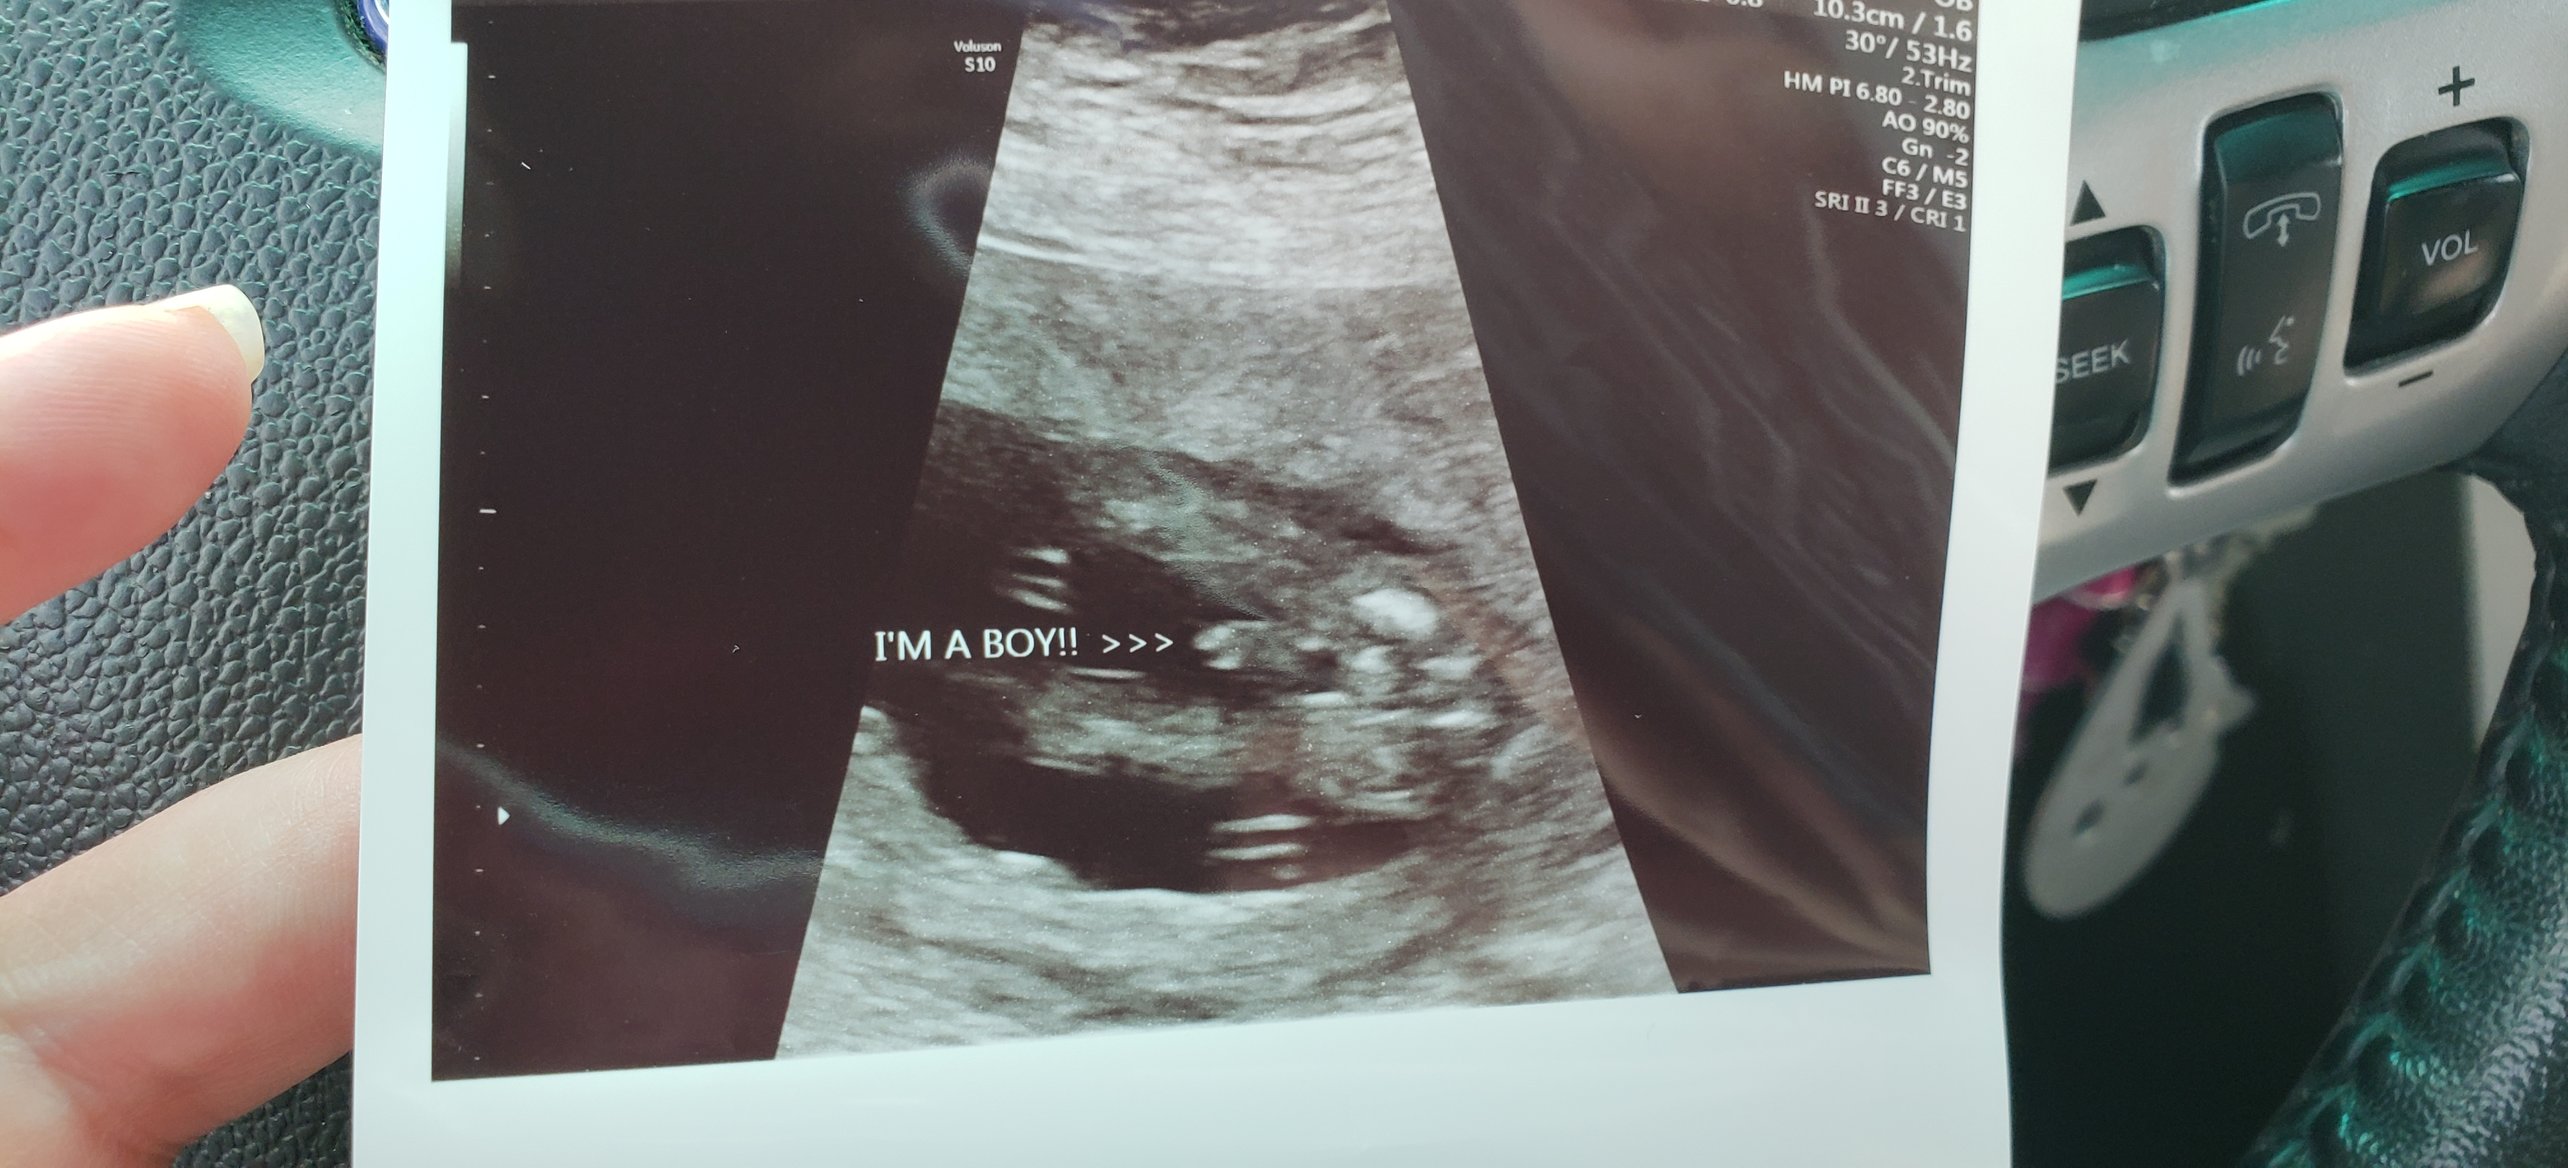

16+2 today and got to see my little man! Yup, found out today I’m having my third boy! Forever outnumbered!! He wouldn’t show us his face. He rolled every time we tried lol but he sure did give us a good hand shot and spread his legs WIDE open haha all junk today. Already a typical boy!